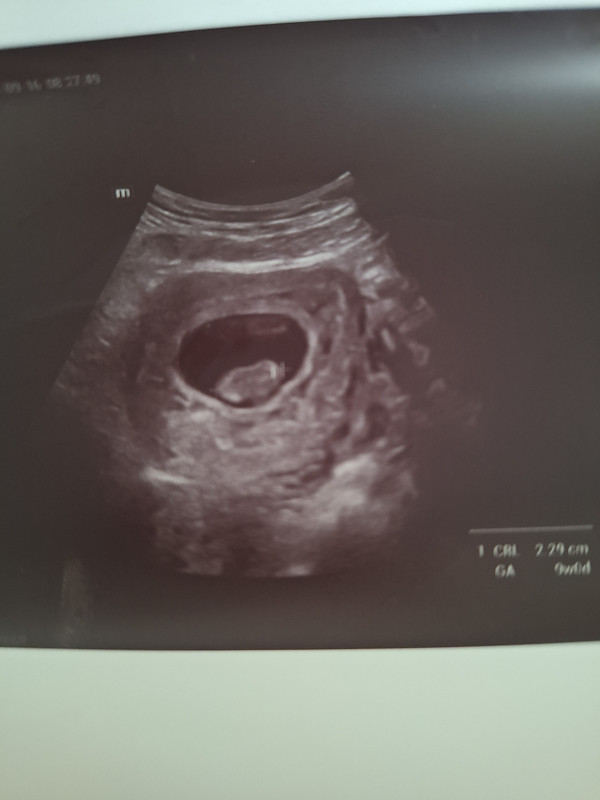

- Nėštumas